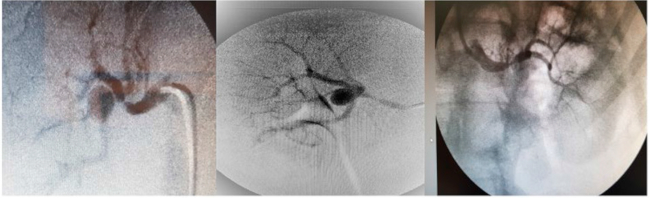

Con sospecha de hipertensión arterial secundaria, probablemente renovascular se realiza Rx. de abdomen y ecografía abdominal que resultaron normales. Por su parte, en la ecografía renal se observa una imagen anecoica en la pelvis renal derecha de 1,95 cm por 1,44 cm. El eco-Doppler de arterias renales presentó una velocidad flujo pico sistólico (VFPS) de la arteria renal derecha (ARD) principal de 210 cm/s (VN <180 cm/s), un índice de resistencia (IR) mayor de 0,7 (VN <0,70), tiempo de aceleración de 0,13 cm/s (VN <0,1). La arteria renal izquierda (ARI) principal tiene una VFPS de 173 cm/s y un IR igual a 0,65. Se realiza una angiografía por sustracción digital renal en la que se observa una lesión grave en el tercio medio de la ARI y otra lesión grave en el tercio medio y pos de la ARD; se objetiva un aneurisma sacular de cuello estrecho en la bifurcación de la AR principal derecha. Tras valorar las opciones terapéuticas, se optó por realizar un tratamiento endovascular que consiste en la exclusión endovascular del aneurisma y la embolización con 5 espirales (coils) (Barricade): 1 de 9 × 30, 2 de 8 × 27 y 2 de 7 × 19 mm, con lo que queda compactado el aneurisma. A continuación, se realiza una angioplastia de AR principal derecha con colocación de stent de 4,30 mm × 16 mm. Al mes siguiente, se practica una angioplastia con colocación de stent Corflex de 4,0 mm × 16 mm a la AR principal izquierda.

La evolución de la paciente fue satisfactoria luego de la intervención: Eco-Doppler color de arterias renales: ARD: VFPS: 170 cm/s, (IR) 0,63; ARI: VFPS: 165 cm/s, (IR) 0,60 y MAPA: HTA sistólica diurna/nocturna, grado I non dipper. Al año, una angiografía selectiva renal fue normal. La paciente continúa normotensa y en tratamiento con carvedilol, amlodipina, aspirina, estatinas y suspende clopidogrel.